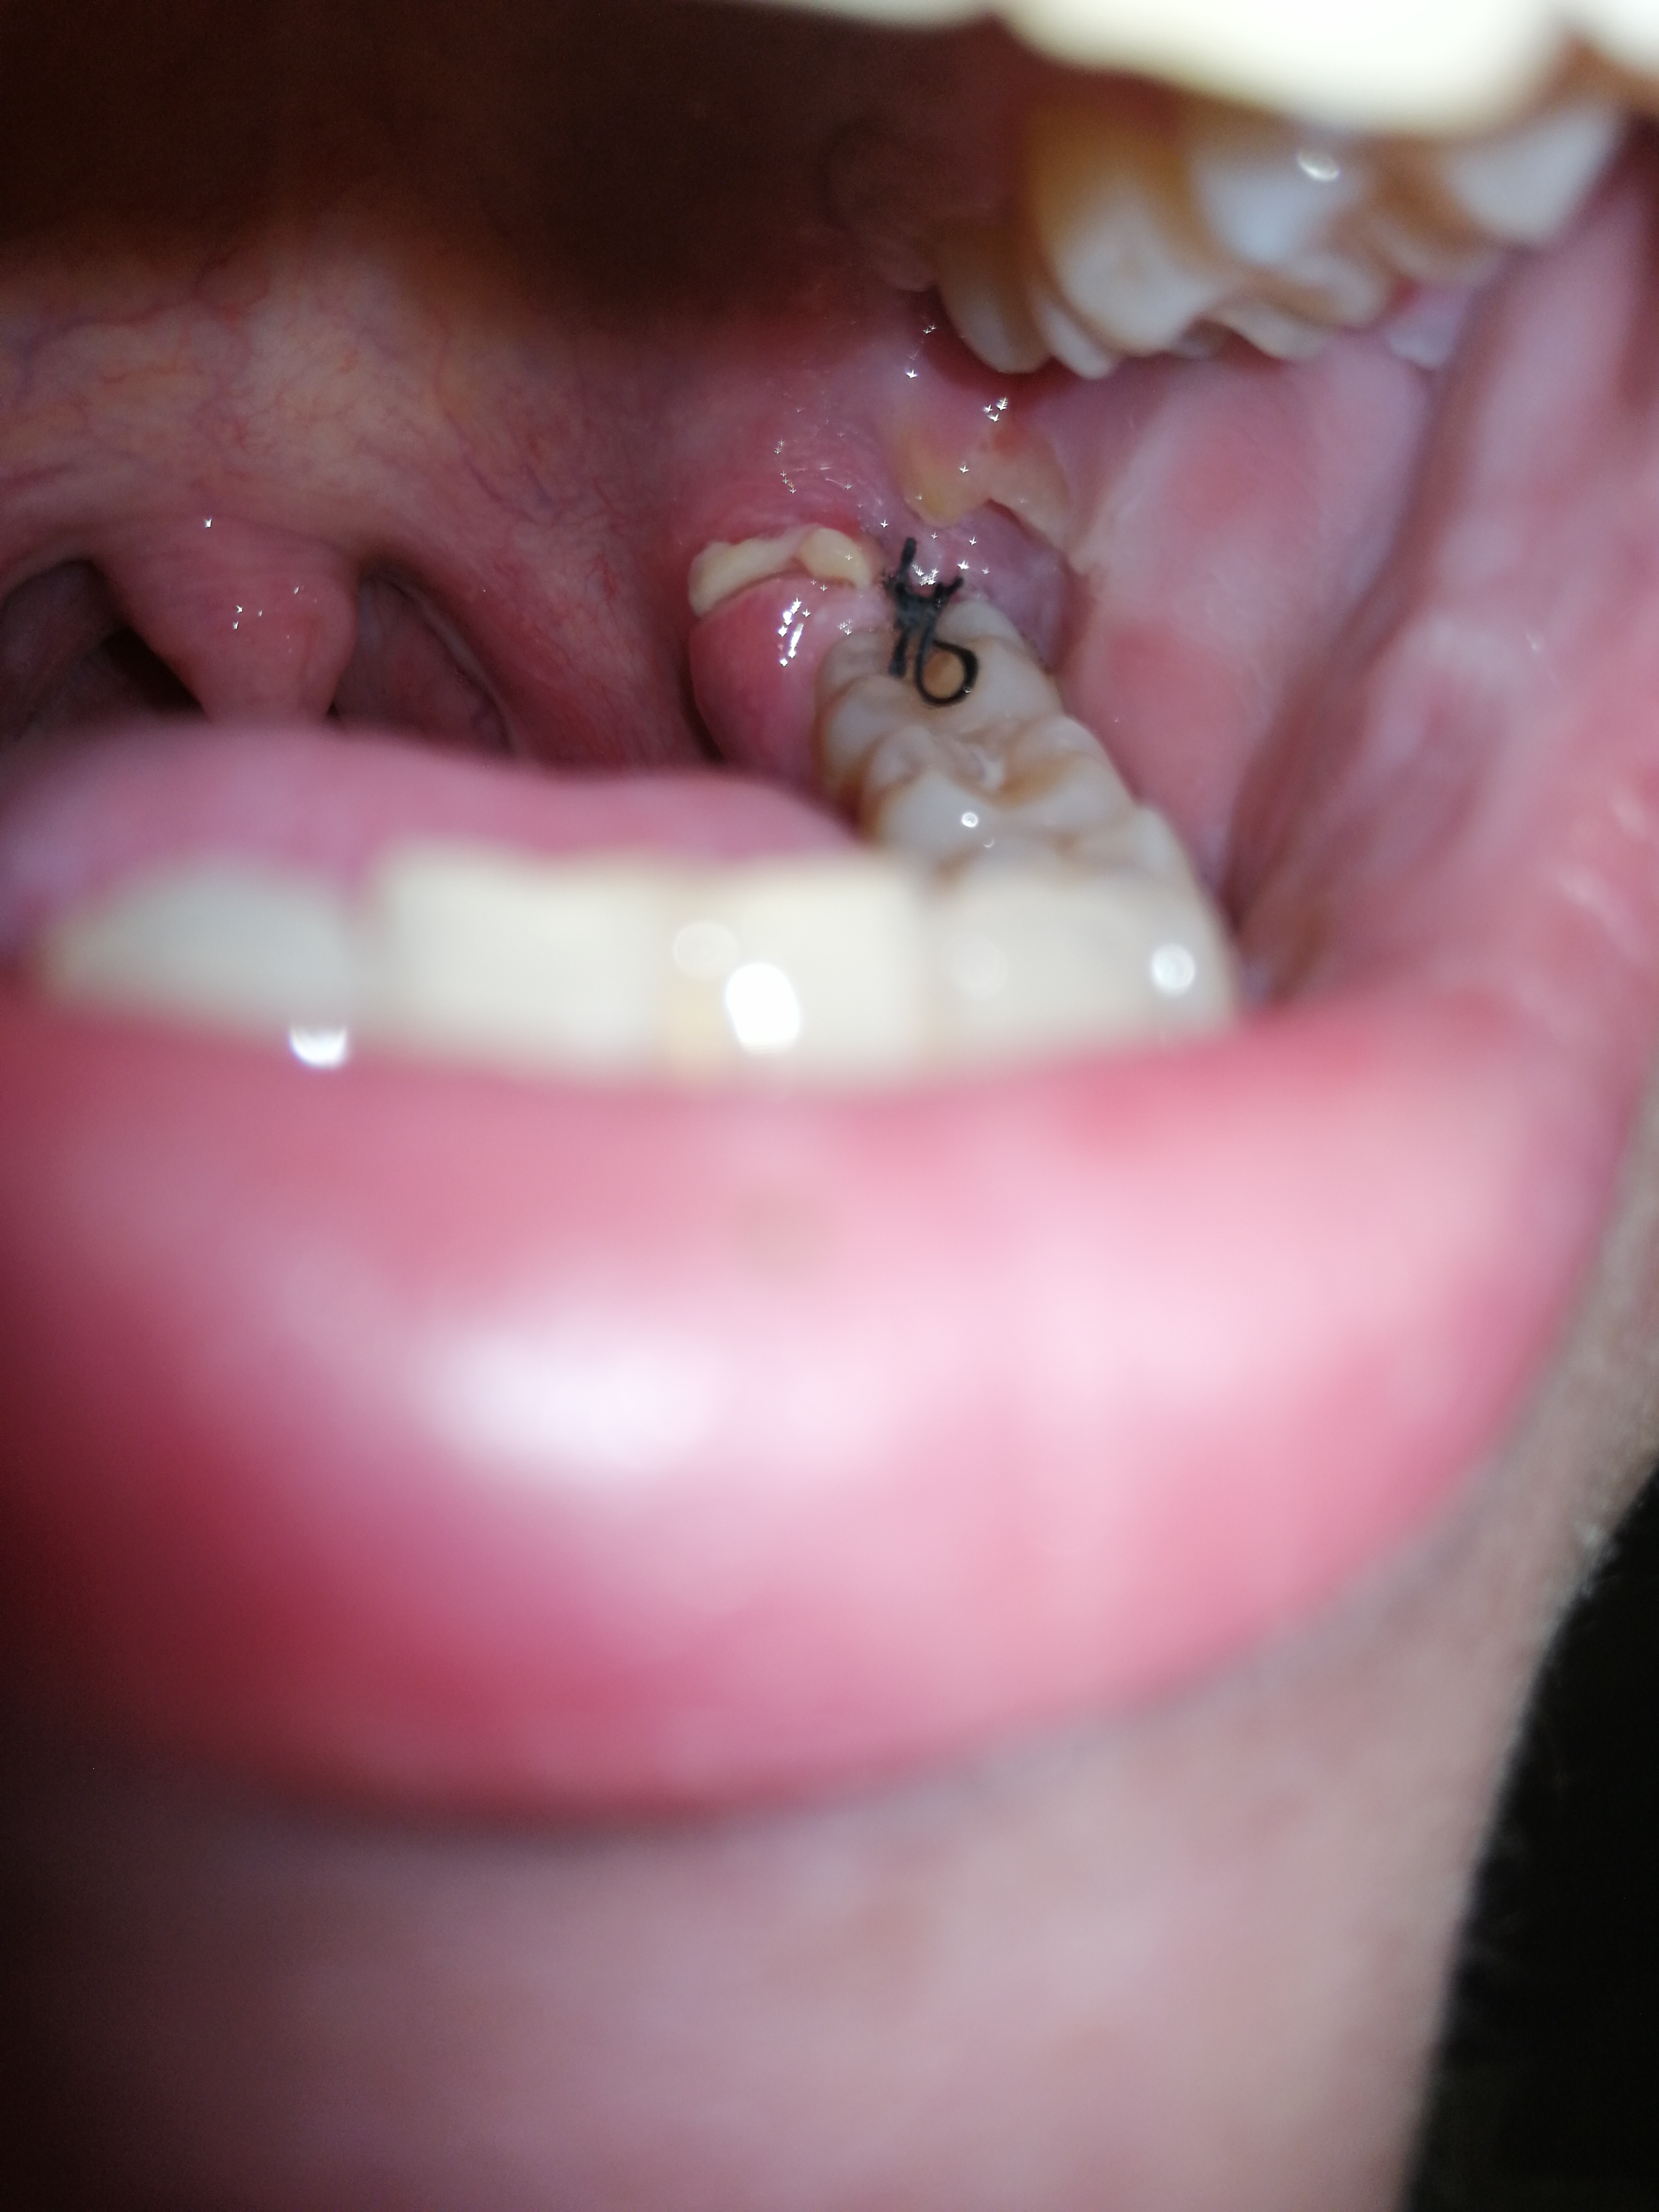

Ist Meine Wunde Nach Weisheitszahn Op Entzundet Gesundheit Und Medizin Weisheitszahne Weisheitszahn Op